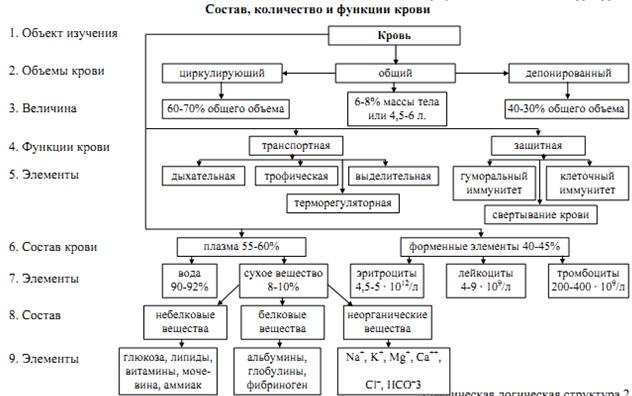

ФІЗІОЛОГІЯ КРОВІ

ФІЗІОЛОГІЯ КРОВІ

| Формений елемент | Фізіологічний показник | Зрушення показника | |||||||||||||||

| чоловіки | жінки | збільшення | зменшення | ||||||||||||||

| Еритроцити | 4 – 5 10 \л | 3,9 – 4,7 10/ л | еритроцитоз | анемія | |||||||||||||

| Гемоглобін | 130 – 160 г\л | 120 – 140 г \л | |||||||||||||||

| Лейкоцити | 4 – 5 10 /л | лейкоцитоз | лейкопенія | ||||||||||||||

| |||||||||||||||||

| Тромбоцити | 180 – 320 10 \ л | тромбоцитоз | тромбопенія | ||||||||||||||

| ШОЕ | 1 -10 мм\год | 2-15 мм\год |

Гемопоез – фізіологічний процес утворення, розвитку та дозрівання клітин крові.

І клас – стовбурові клітини – дають початок всім форменим елементам крові.

ІІ клас – уніпотентні клітини – дають початок двум направленням: мієлопоез та лімфопоез.

ІІІ клас – розвиваються по одному направленню, дають 8 початків утворення клітин крові.

ІV клас – бласти, клітини крові морфологічно відрізняються між собою.

V клас – дозріваючі клітини.

VІ клас – зрілі клітини.

При гострому лейкозі спостерігається збільшення клітин класу 1 – 3.

При хронічному лейкозі спостерігається збільшення баластних клітин.